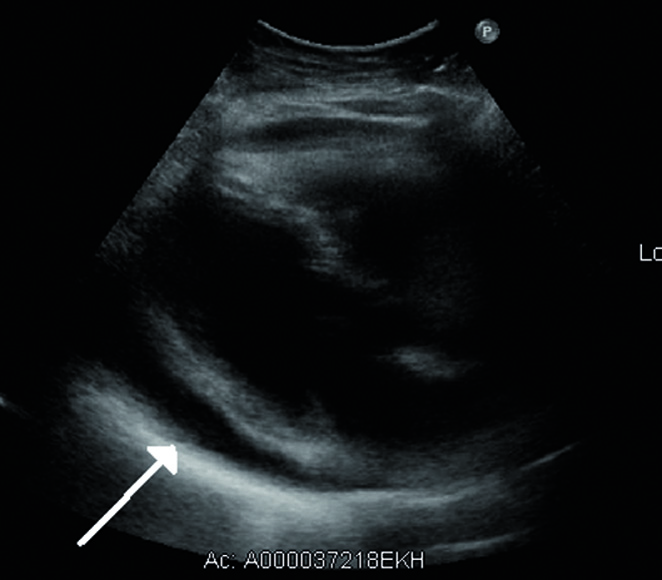

Echokardiographisch lässt sich die Flüssigkeitsansammlung im Herzbeutel sehr deutlich darstellen.

© wikimedia/James Heilmann. Echokardiographisch lässt sich die Flüssigkeitsansammlung im Herzbeutel sehr deutlich darstellen. © wikimedia/James Heilmann.